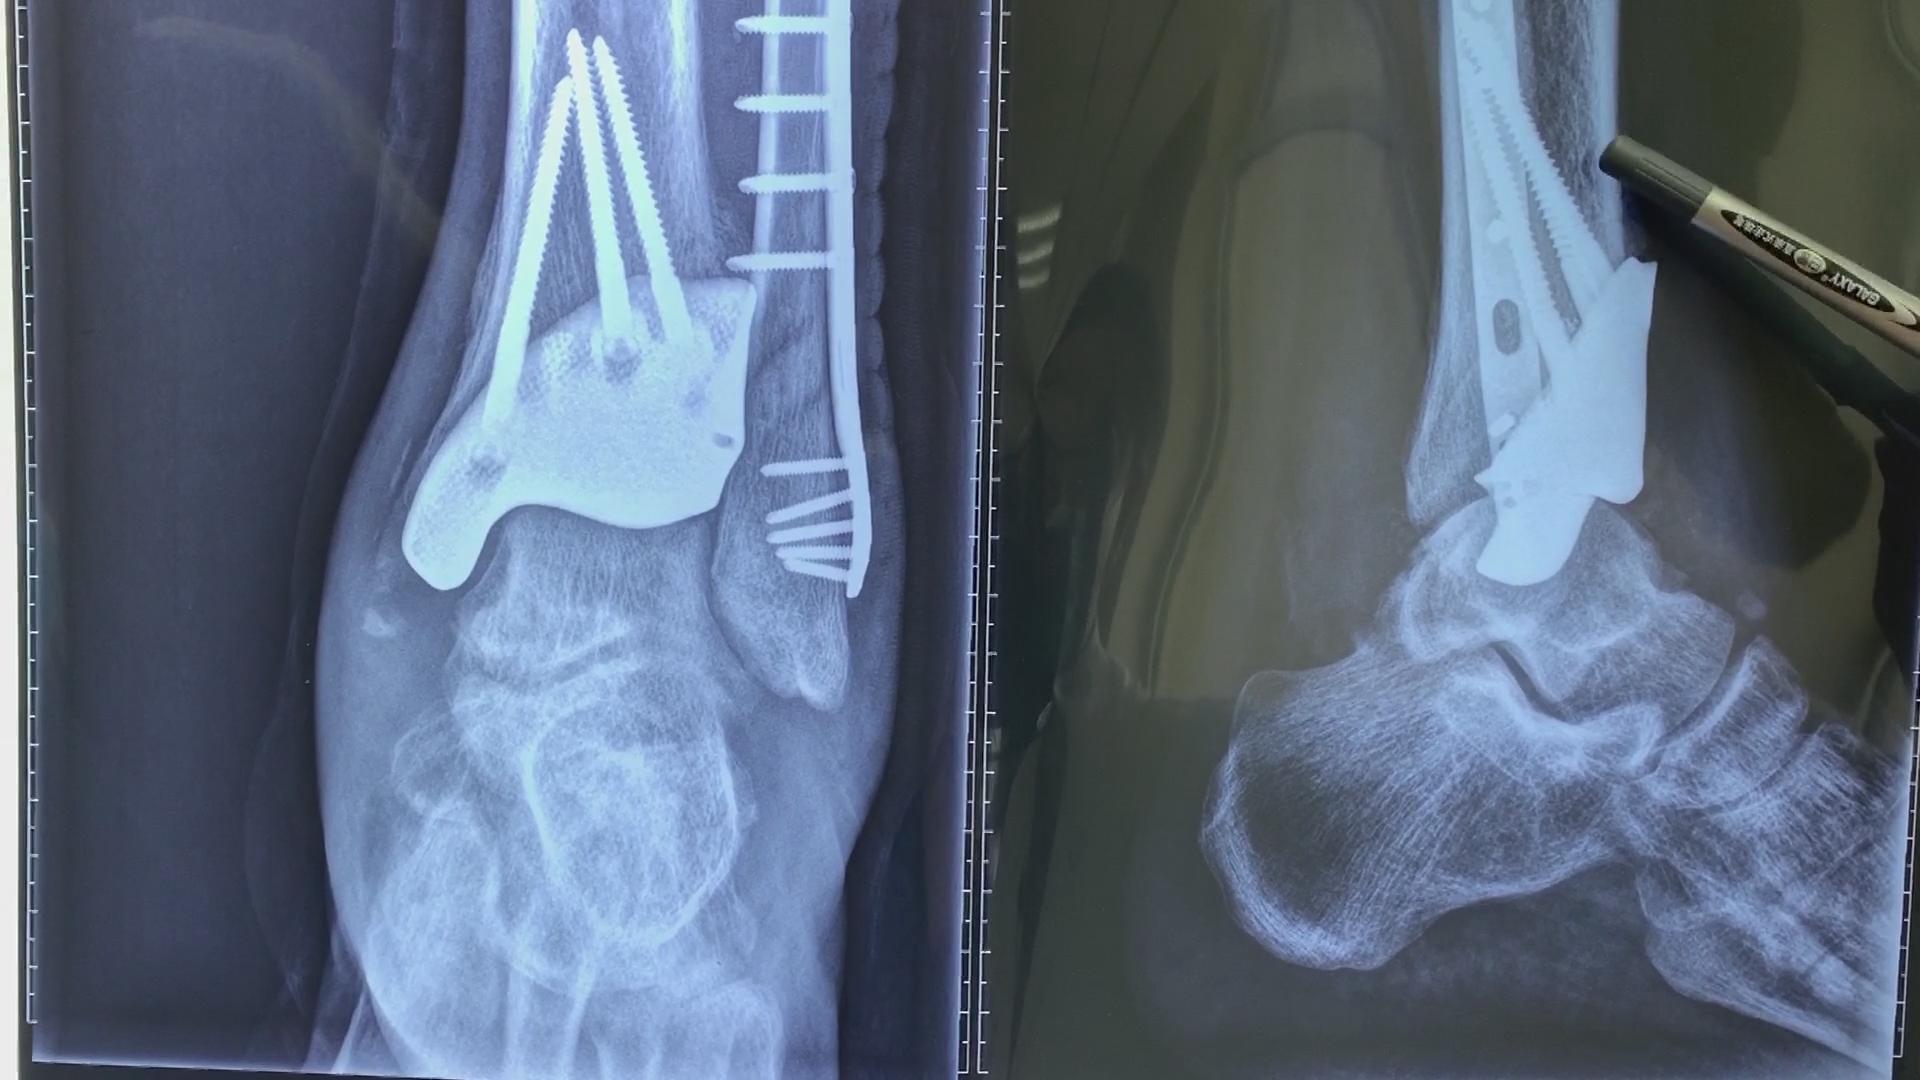

打球崴到脚踝左外踝骨折骨折,请大家看看我现在是什么情况.

19年11.27号左外踝撕脱性骨折